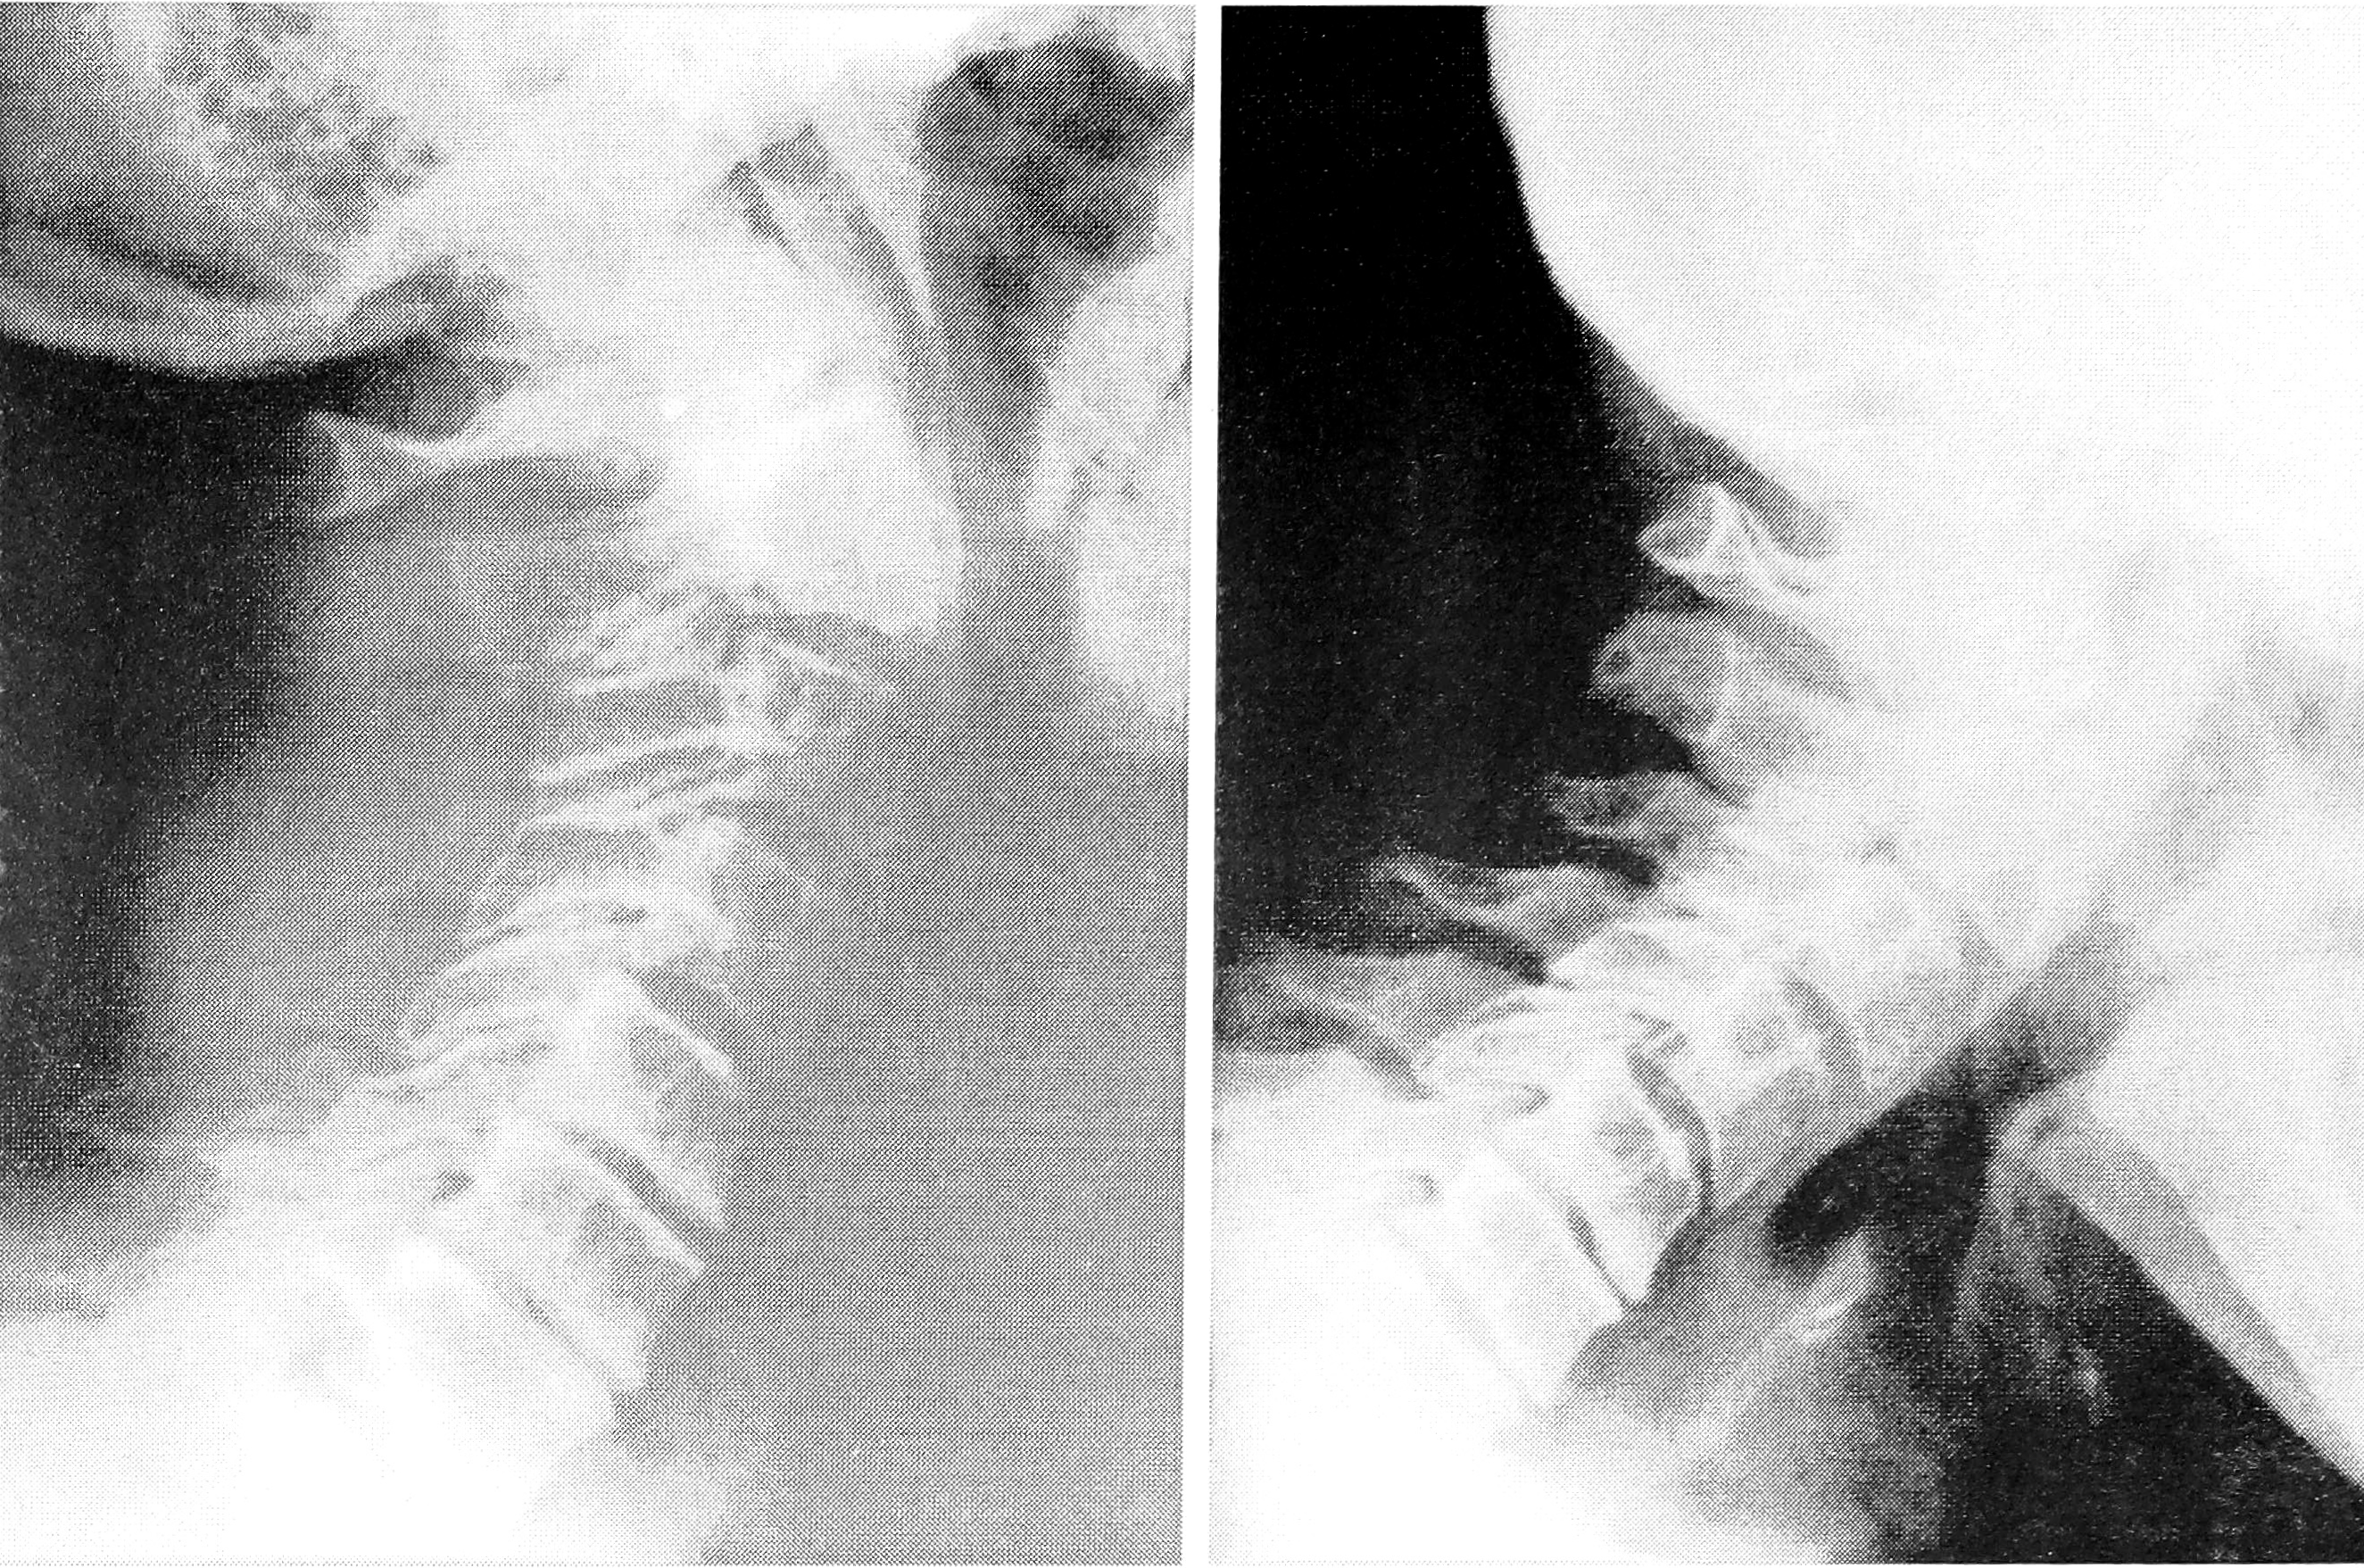

Больной К., 39 лет, поступил в клинику на 12-е сутки после травмы, полученной в автодорожной аварии, с симптомами ушиба бульбарного отдела продолговатого мозга. На рентгенограммах шейного отдела позвоночника выявлен перелом корня дуги С2 с обеих сторон со смещением тела С2 и краниального отдела позвоночника вперед до 1/2 переднезаднего размера тела СЗ без нарушения соотношения в дугоотростчатых суставах С2—СЗ и суставах атлантоаксиального сочленения. Диагноз: травматический спондилолистез С2 II степени; ушиб бульбарного отдела продолговатого мозга. Лечение проводилось методом гало-тракции. 21.11.89 — репозиция, стабилизация (см. рис. 3, a на вклейке). Гало-аппарат демонтирован 05.02.90: остаточное смещение тела С2 в пределах 1/5 переднезаднего размера тела СЗ (рис. 3, б). Сформировался спонтанный костный блок тел С2—СЗ. Неврологический синдром регрессировал. Спустя еще 4 нед больной приступил к работе.

Рис. 3. Рентгенограммы больного К. Диагноз: травматический спондилолистез С2 II степени. а — начальный этап лечения методом гало-тракции; б — через 2,5 мес.